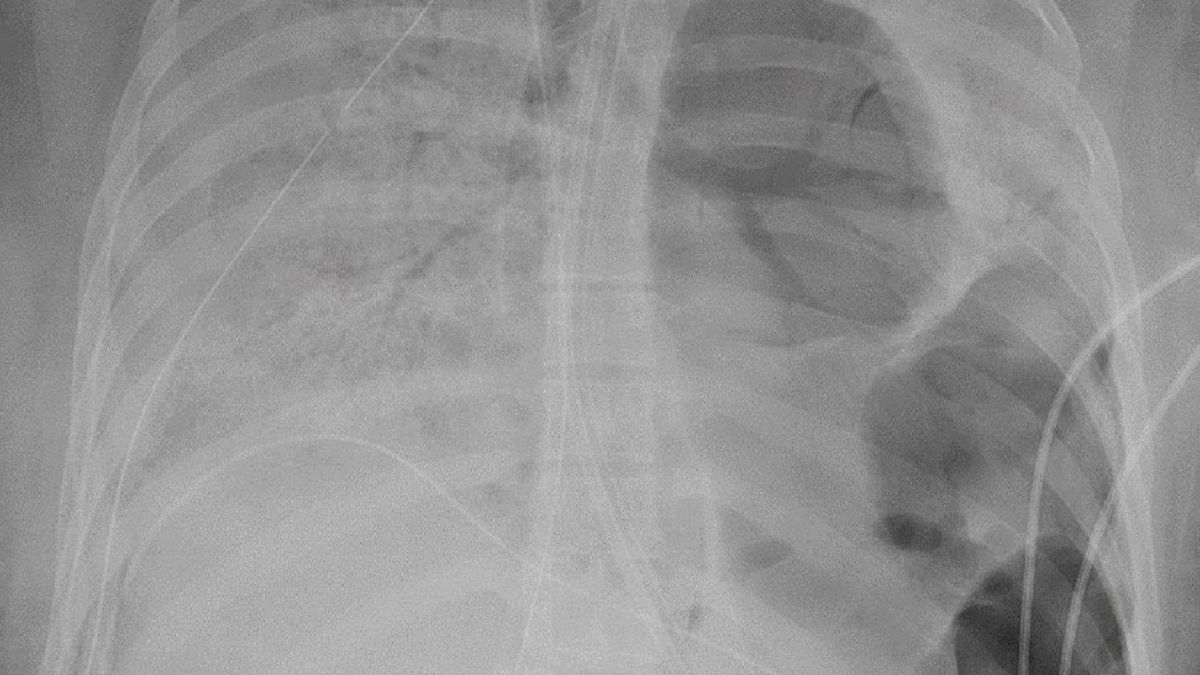

Koronawirus zostawił pacjentkę z podziurawionymi płucami. Organy były praktycznie w zaniku i dlatego lekarze zdecydowali się na trudną operację przeszczepu. Wcześniej upewnili się, że 20-latka całkowicie wyzdrowiała z COVID-19.

10-godzinna operacja była trudna, ponieważ przez wirusa jej płuca były pełne dziur i prawie wtopiły się w ścianę klatki piersiowej - powiedział dr Ankit Bharat, prowadzący operację.